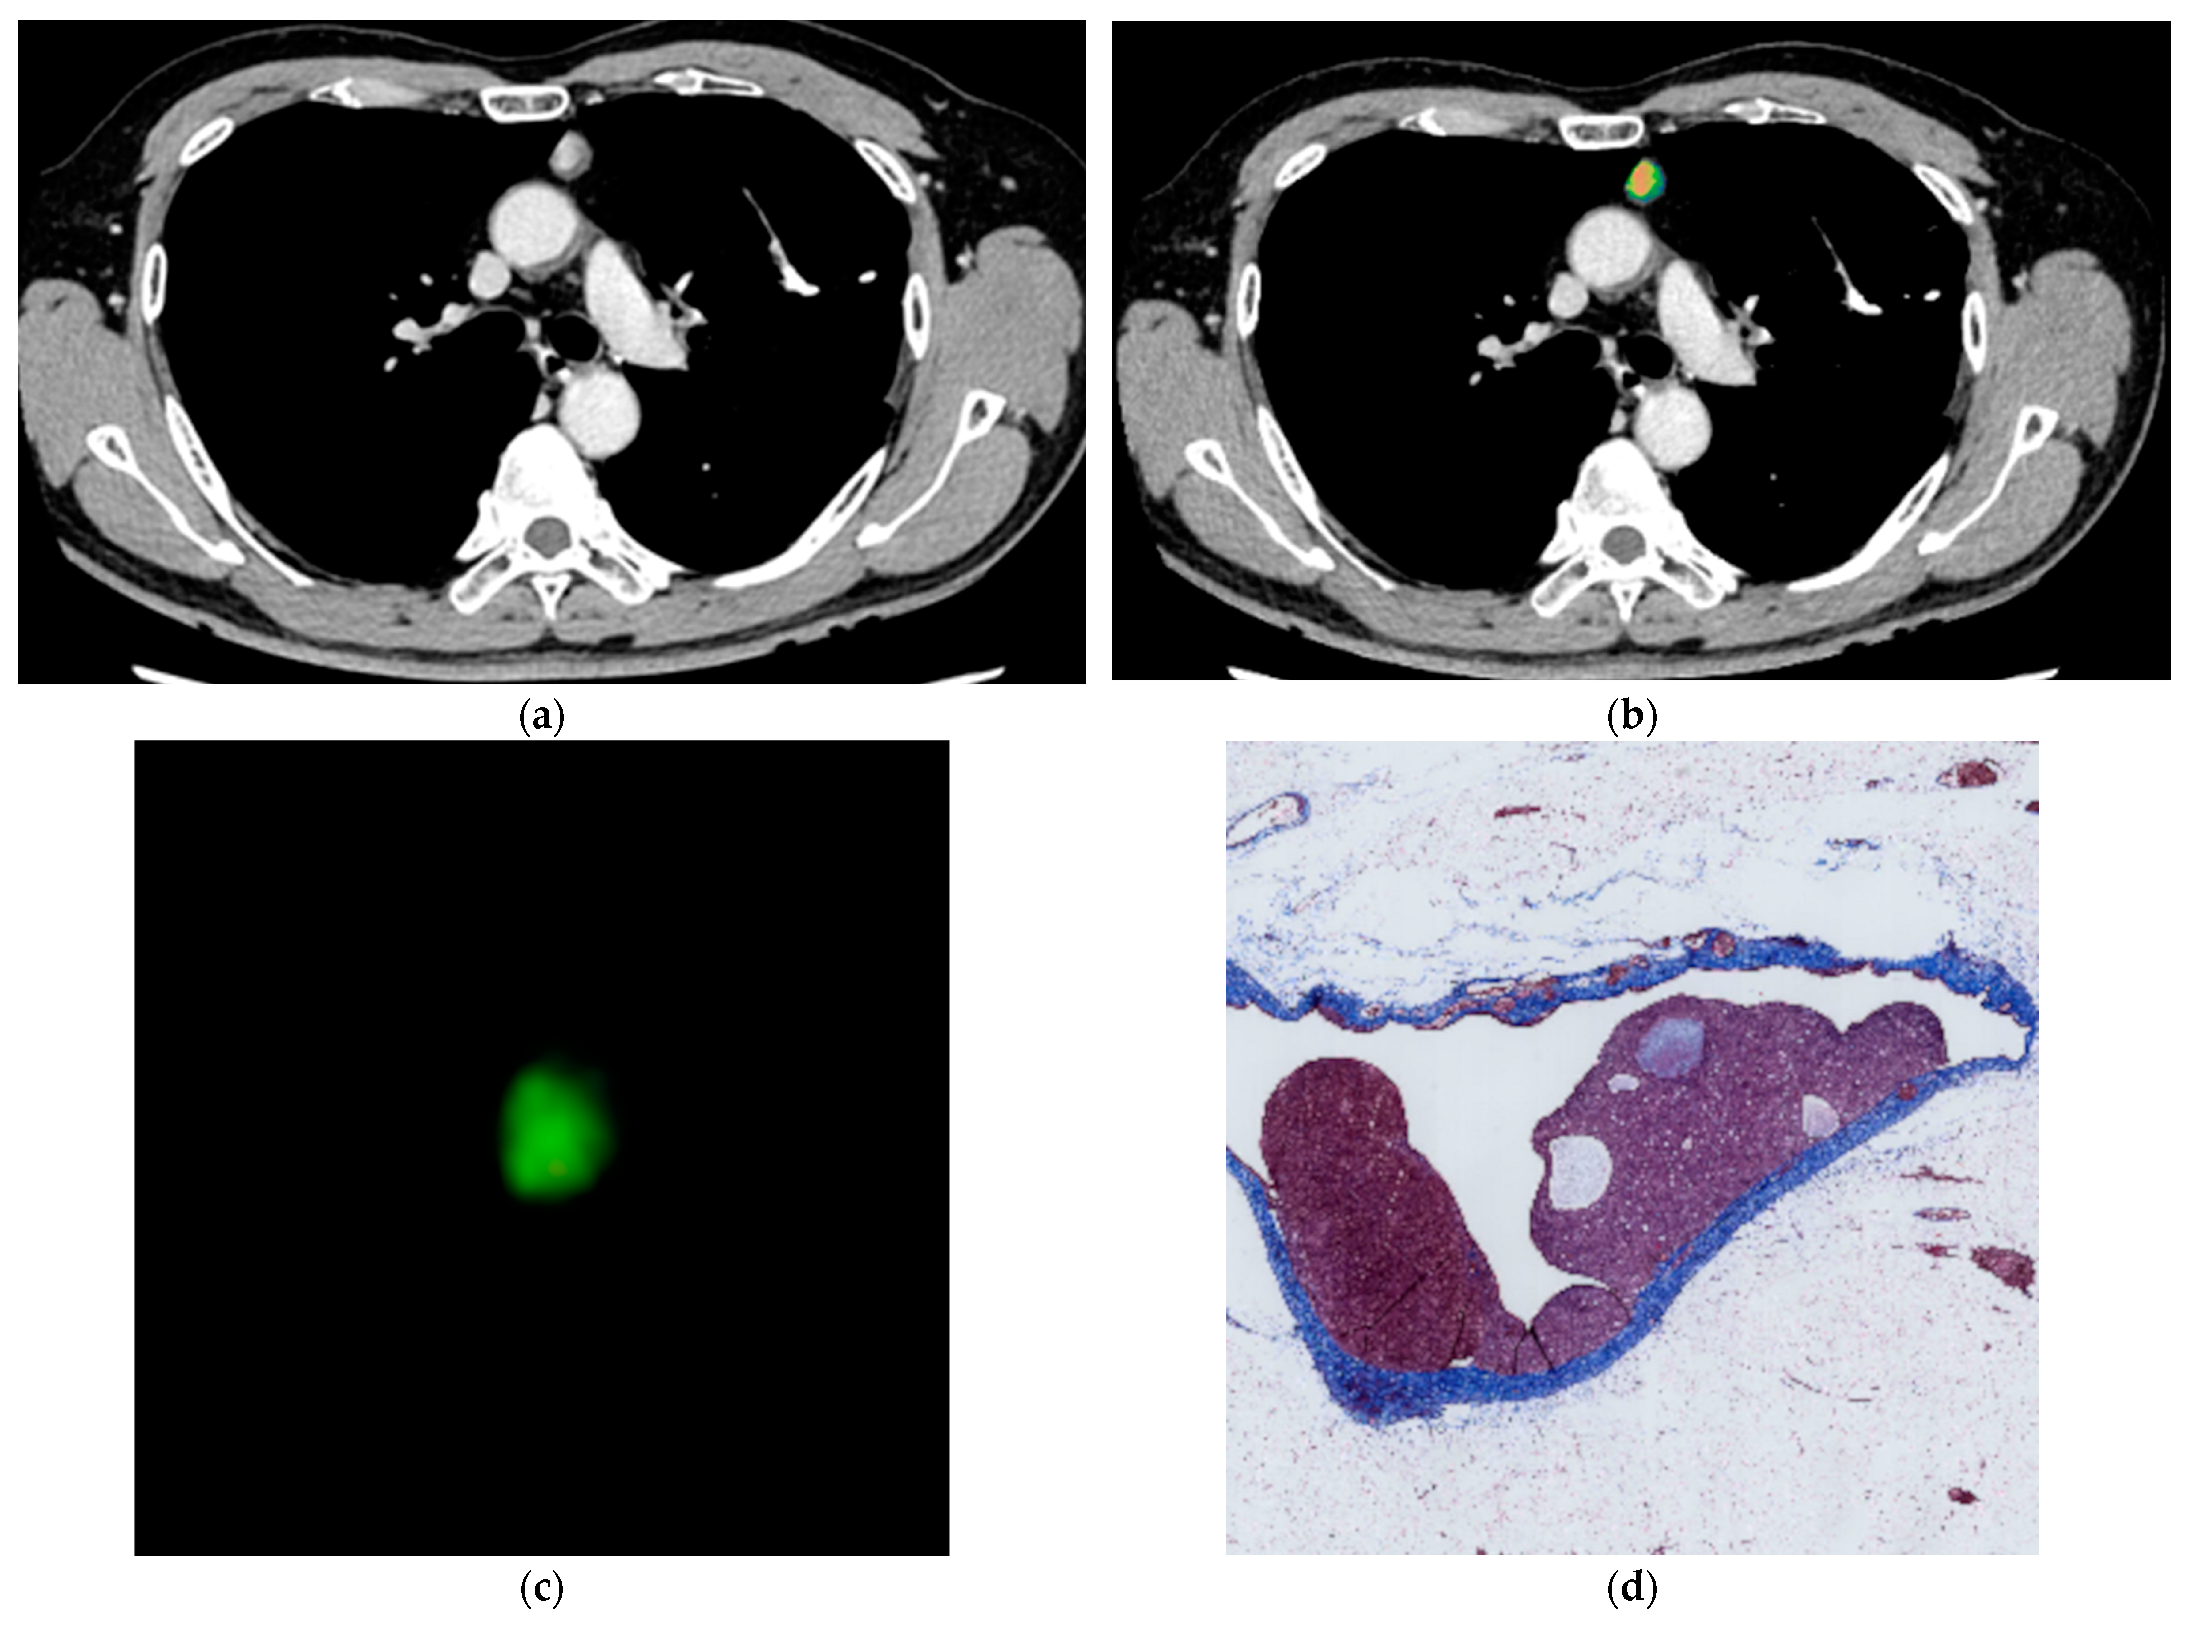

2.3. Image Analysis

2.4. Histological Evaluation